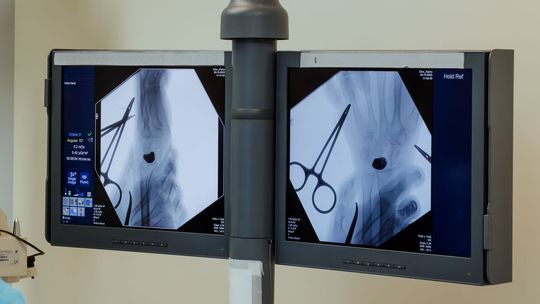

Przygotowania do operacji trwały rok. Lekarze wykonali cyfrowy model nadgarstka, na podstawie którego powstał implant z biokompatybilnego stopu tytanu. Powierzchnie odpowiedzialne za ruch i kontakt ze stawem wygładzono lub pokryto powłoką diamentopodobną, aby zminimalizować tarcie.

Zabieg przeprowadził zespół pod kierownictwem dr. n. med. Piotra Piecha.